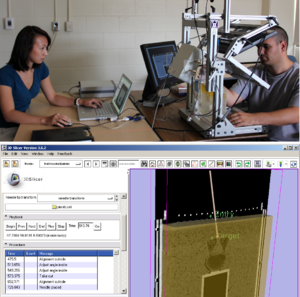

- 4.45 Spinal Curvature Measurement by Tracked Ultrasound Snapshots

- 5.1 Tracked Ultrasound Snapshots in Percutaneous Pedicle Screw Placement Navigation: A Feasibility Study